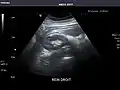

Renal ultrasonography

Ultrasound scan of a kidney (right side)

Ultrasonography of the kidneys is essential in the diagnosis and management of kidney-related diseases. The kidneys are easily examined, and most pathological changes in the kidneys are distinguishable with ultrasound.[7]

Kidneys: Right and left kidneys measure 11.5 cm and 12 cm in length respectively. No hydronephrosis. Small left lower pole kidney cyst.